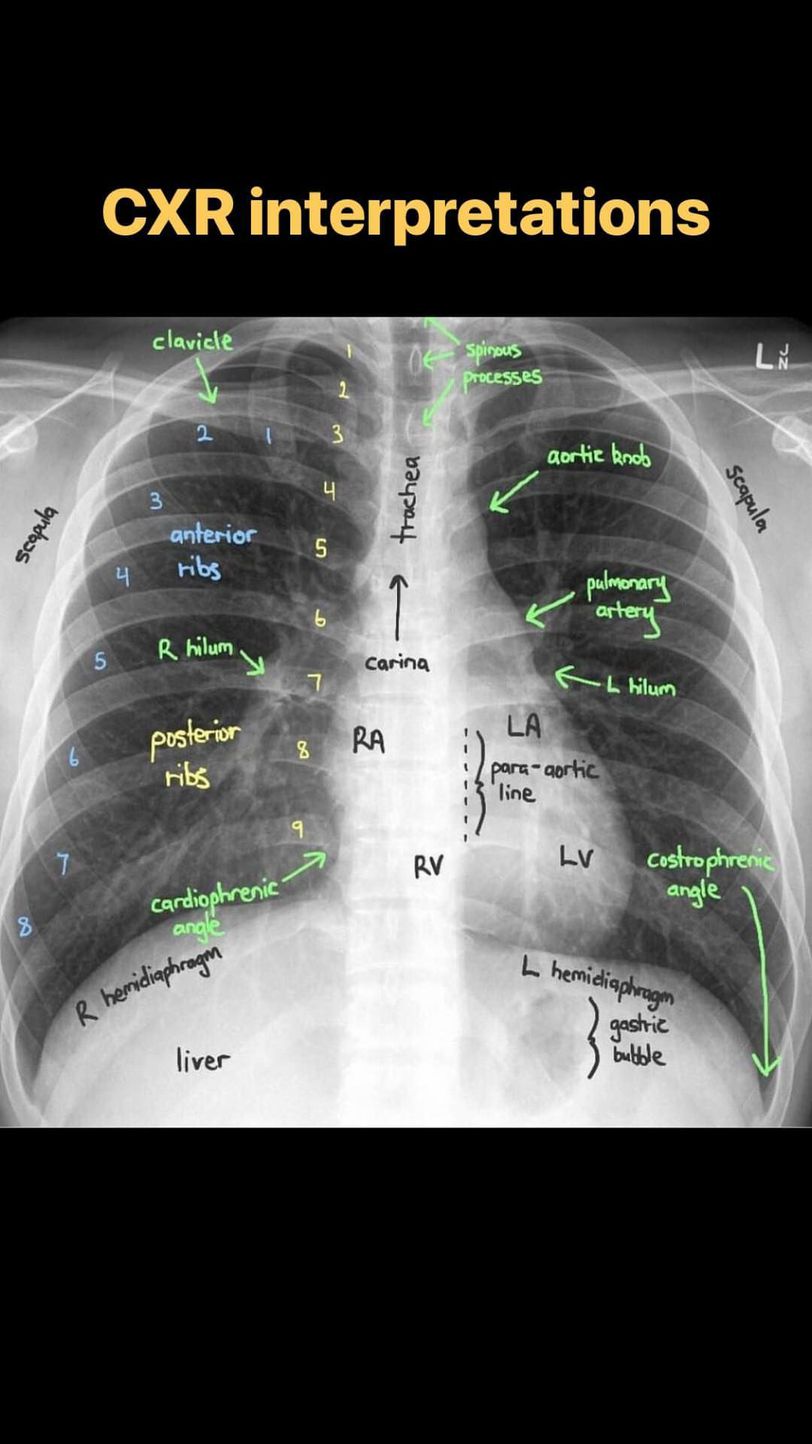

CXR interpretation

Anatomy

Radiography

Ctscan